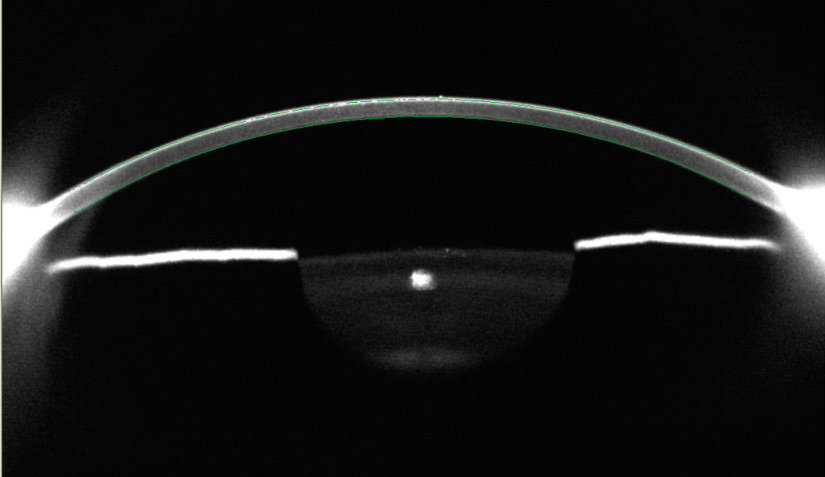

Combinant la topographie Placido et Scheimpflug, le TMS-5 de TOMEY permet l’analyse complète de la face antérieure et postérieure de la cornée.

Image Scheimpflug

| Diamètre d’observation | 13.6 mm |